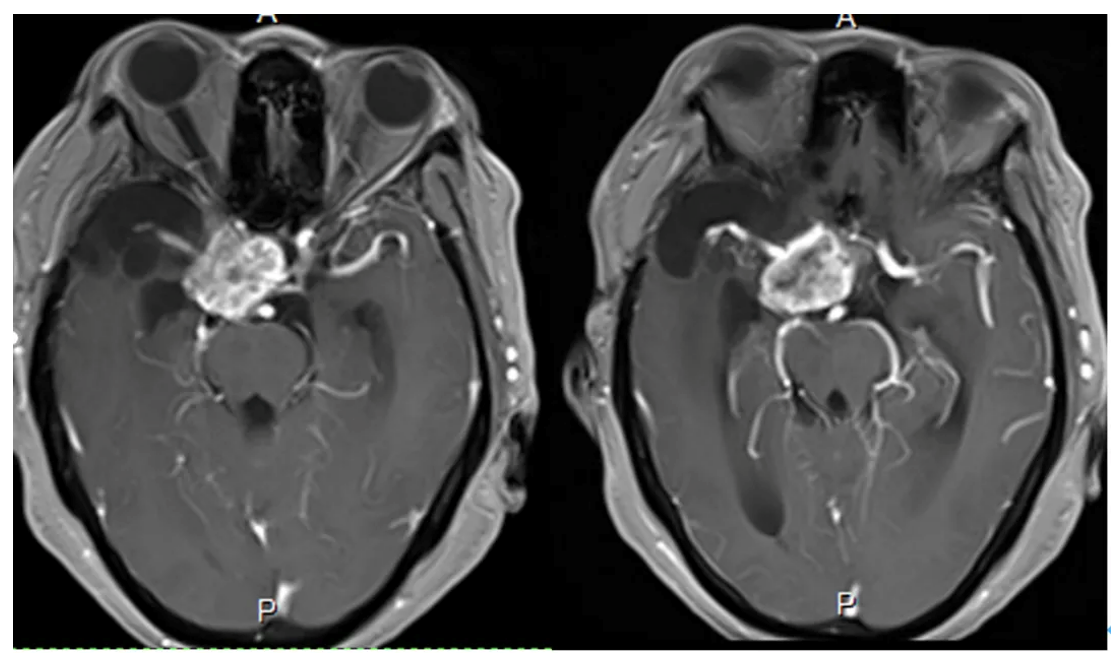

Cranial MRI enhanced

1. MRI T1 and T2 images showed a tumor in the left saddle region with long T1 and short T2 signals. The tumor was solid and encircled the internal carotid artery and branch vessels.

2. Enhanced axial and coronal-sagittal views showed that the tumor was unevenly enhanced, which was located in the saddle region, invaded the right cavernous sinus, and encircled the internal carotid artery and its branches and perforating vessels.